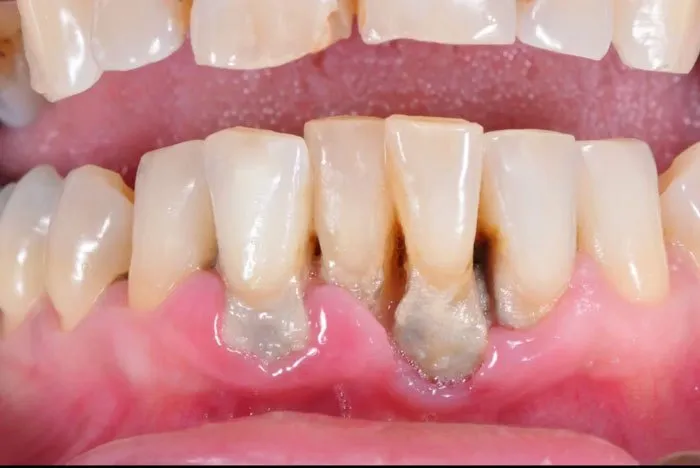

Vệ sinh răng miệng luôn là nền tảng quan trọng nhất trong việc phòng ngừa và hỗ trợ chữa nha chu tại nhà. Không chỉ đơn thuần là chải răng, mà còn là việc duy trì thói quen vệ sinh sạch sẽ, đúng cách để loại bỏ mảng bám, vi khuẩn gây bệnh, giúp giảm thiểu viêm nhiễm nướu và tổn thương răng.

Một số người nghĩ rằng đánh răng chỉ cần qua loa là đủ, nhưng thực tế, cách đánh răng đúng cách mới giúp loại trừ tối đa vi khuẩn và mảng bám, từ đó hỗ trợ giảm triệu chứng nha chu rõ rệt hơn. Chọn các dụng cụ vệ sinh phù hợp và duy trì thói quen đều đặn là điều kiện cần để bảo vệ sức khỏe răng miệng hiệu quả.

Các biện pháp tự chăm sóc răng miệng như vệ sinh đúng cách, chế độ ăn uống hợp lý hay các phương pháp thiên nhiên chỉ hỗ trợ làm giảm triệu chứng, ngăn chặn sự tiến triển của nha chu mà không thể chữa khỏi hoàn toàn. Đây là bước đệm để duy trì tình trạng hiện tại, tránh cho bệnh nặng thêm.

Chữa nha chu tại nhà phù hợp cho những giai đoạn mới phát bệnh hoặc để duy trì sự ổn định sau điều trị chuyên sâu. Tuy nhiên, nếu xuất hiện các triệu chứng như chảy máu chân răng kéo dài, hôi miệng nặng, nướu sưng to hoặc răng lung lay thì cần đi khám nha sĩ ngay lập tức để có phương án điều trị phù hợp.